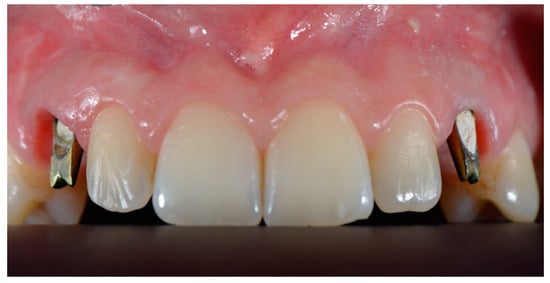

:1. Introduction

2. Materials and Methods

2.3. Surgical and Prosthetic Workflow

2.4. Outcome

3. Results